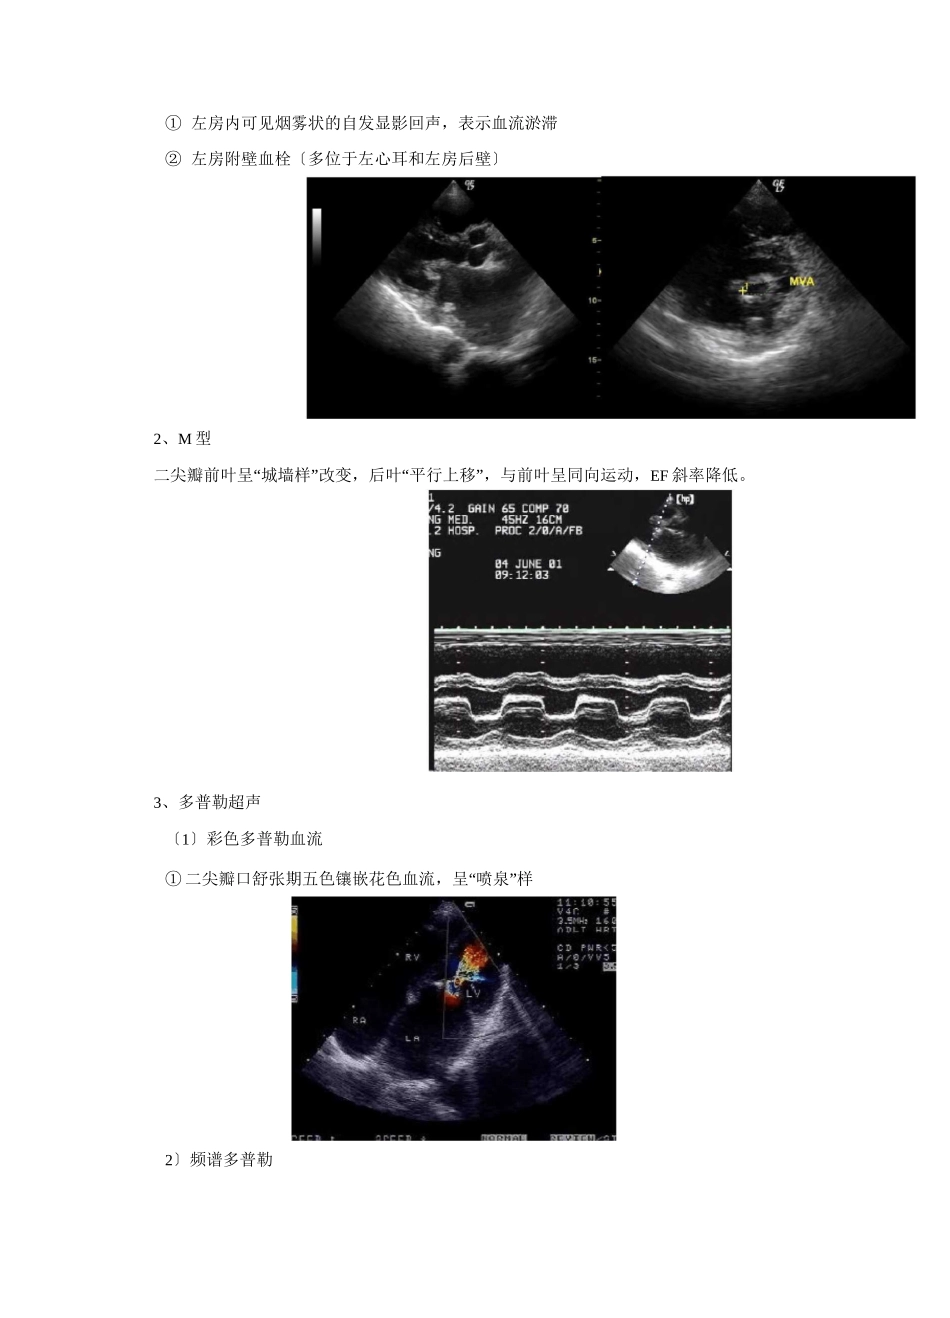

心脏瓣膜病课件目的与要求掌握:二尖瓣狭窄的超声诊断要点及定量分析;二尖瓣脱垂的超声诊断要点;主动脉瓣狭窄的超声诊断要点及定量分析;感染性心内膜炎的二维超声表现。熟悉:二尖瓣关闭不全、主动脉瓣关闭不全的超声诊断要点及定量分析;各种正常人工瓣膜的超声表现;肺动脉压的测量方法及肺动脉高压的诊断标准。了解:各类心脏瓣膜病的病因、病理解剖和病理生理;人工瓣膜并发症及其超声表现;超声心动图新技术在心脏瓣膜病诊断中的应用。一、二尖瓣狭窄〔mitralstenosis〕〔一〕病因、病理解剖1、风湿热是最常见病因2、二尖瓣交界处粘连和融合,瓣膜增厚、变形、钙化,腱索和乳头肌增粗、缩短、融合3、分型:隔膜型、漏斗型〔二〕病理生理1、慢性肺淤血期2、肺动脉高压期〔三〕超声表现及诊断要点1、二维〔1〕直接征象①二尖瓣增厚、回声增强,以瓣尖明显,瓣膜交界处粘连融合,严重者可见腱索和乳头肌增粗、缩短、融合②舒张期二尖瓣开放受限③瓣口呈“鱼嘴状”或不规则形,面积缩小〔2〕间接征象①左房增大②右室增大,肺动脉及其分支增宽〔3〕继发性改变①左房内可见烟雾状的自发显影回声,表示血流淤滞②左房附壁血栓〔多位于左心耳和左房后壁〕2、M型二尖瓣前叶呈“城墙样”改变,后叶“平行上移”,与前叶呈同向运动,EF斜率降低。3、多普勒超声〔1〕彩色多普勒血流①二尖瓣口舒张期五色镶嵌花色血流,呈“喷泉”样2〕频谱多普勒PADP:肺动脉舒张期压RVDP:右室舒张期压〔四〕二尖瓣狭窄的定量诊断1.直接测量法2.压差减半时间法:MVA(cm2)=220/PHT(ms)3.连续方程法4.跨瓣压差法5.多普勒近端血流会聚法轻度狭窄:>1.5cm2中度狭窄:1.0~1.5cm2重度狭窄:<1.0cm2〔五〕肺动脉高压的定量检测1、肺动脉压的测量方法三尖瓣和肺动脉瓣关闭不全时,可通过反流频谱测量肺动脉压PASP=RVSP=RAP+PG〔三尖瓣〕PADP=RVDP+PG=RAP+PG〔肺动脉瓣〕PG(mmHg)=4V2PASP:肺动脉收缩期压RVSP:右室收缩期压RAP:右房压〔约为10mmHg)2、肺动脉高压诊断标准PASP>30mmHg3、肺动脉高压分型①二尖瓣正常双峰样血流频谱消失,呈现“城墙样”宽带、充填频谱,峰值流速增轻型:30mmHgWSPAP<40mmHg中型:40mmHgWSPAPv7OmmHg重型:>70mmHg六〕超声新技术的应用1、经食管超声心动图2、三维超声心动图二、二尖瓣关闭不全〔mitralinsufficiency〕〔一〕病因二尖瓣装置中任何一部分的功能失调和器质性损害均可导致二尖瓣关闭不全1、风湿热是最常见病因2、退行性〔二尖瓣脱垂、二尖瓣环钙化等〕3、感染性心内膜炎〔二〕病理生理左心系统容量负荷增加的病理生理改变〔三〕超声表现及诊断要点1、二维〔1〕二尖瓣增厚、回声增强、钙化,腱索、乳头肌粘连融合、缩短〔2〕收缩期二尖瓣前后叶对合不良,可见缝隙〔3〕左房、左室增大2、M型二尖瓣前后叶曲线CD段呈双线3、多普勒超声〔1〕彩色多普勒血流收缩期二尖瓣口左房侧探及蓝色为主五彩镶嵌反流束2〕频谱多普勒〔四〕定量诊断〔1〕反流束长度轻度:<1.5cm中度:1.5〜2.9cm中重度:3.0〜4.4cm重度:>4.5cm〔2〕反流束面积轻度:<4.0cm2中度:4.0〜8.0cm2重度:>8.0cm2三、二尖瓣脱垂〔mitrialprolapse〕〔一〕病因、病理解剖1、原发性:二尖瓣装置黏液样变性,瓣叶增厚或冗长,腱索过长或断裂,瓣环扩张2、继发性:风湿病变、感染性心内膜炎,冠心病TildDOMS7BCMFn9.4MHr于二尖瓣口左房侧记录到收缩期的高速湍流频5-M-IP!<■-□DRnFR11HE_3IMj^h1D-皿Elr・・AEl-hipiulLMQJUHCHiG.Ml<3SfQ&SffiADM越期临〜《{■Uf?wwf°^durt■IlMt11m%4.4MHLEbMHZSrt・〔二〕超声表现及诊断要点1、二维收缩期二尖瓣一个和/或两个瓣叶脱向左房侧,超过瓣环连线水平2mm以上,伴或不伴有瓣叶增厚;左房、左室增大2、M型二尖瓣前后叶曲线CD段收缩期向下凹陷,呈吊床样改变,与CD两点间的连线距离大于2mm3、多普勒超声〔1〕彩色多普勒血流收缩期二尖瓣口左房侧探及蓝色为主的五彩镶嵌反流束〔2〕频谱多普勒二尖瓣口左房侧记录到收缩期的高速湍流频谱三〕超声新技术的应用1、经食管超声心动图2、三维超声心动图四、主动脉瓣狭窄〔aorticstenosis〕〔一〕病因、病理解剖1、风湿热主动脉瓣...